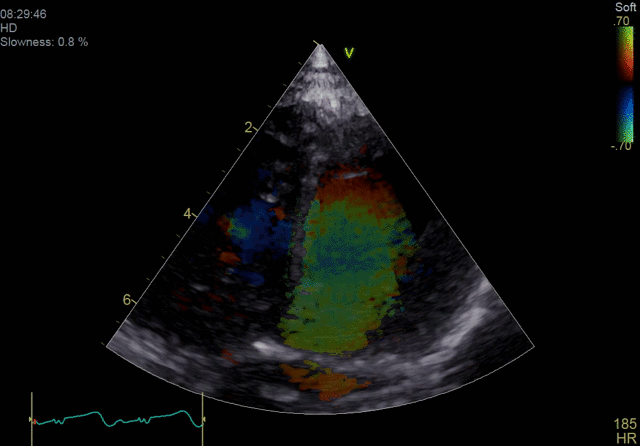

4D color imaging with the 4Vc-D probe